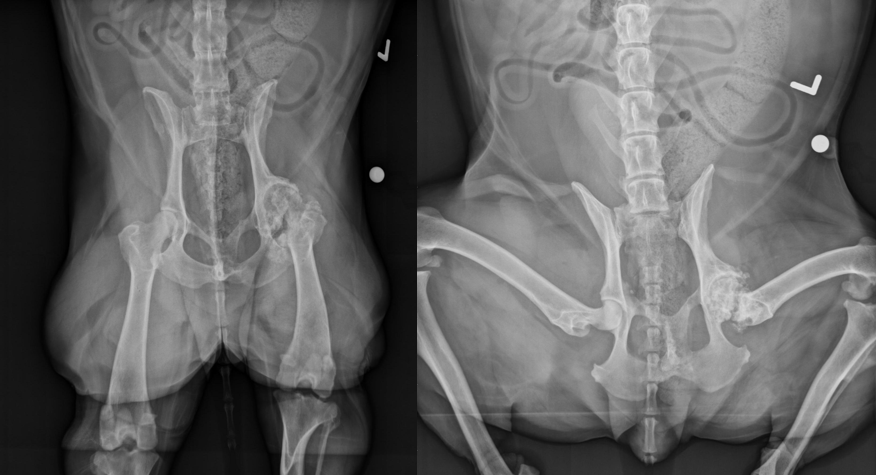

4

Q

12 years old female neutered Labrador

Sudden onset lameness after ball game

Front right leg

A

Multiple fractures in pelvis